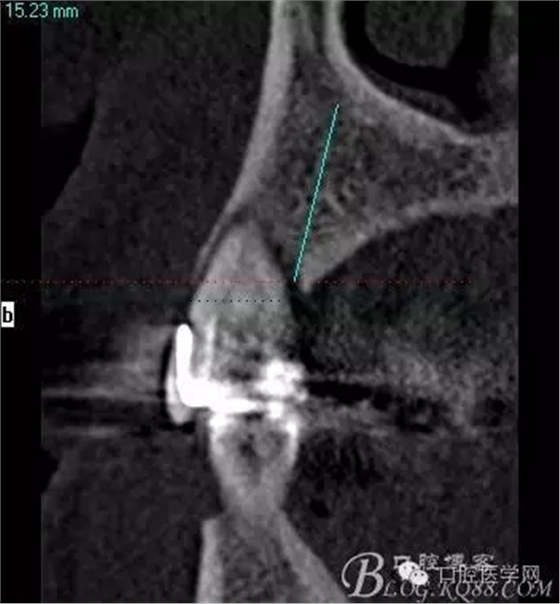

這是初診時(shí)候的CT片截圖。目標(biāo)是14到16固定橋,別的牙齒先慢慢來,那么牙周肯定要做的,哪怕我要把14 16拔了,我也必須先去牙周科刮治。 在這里我感謝我們醫(yī)院的牙周科所有同事幫我們很多。刮治以后的牙齒拔掉即刻種植相對(duì)沒刮治過的牙齒肉芽會(huì)少很多,那么我在手術(shù)時(shí)候速度會(huì)快,會(huì)省力很多,我最討厭去刮很多肉芽,有時(shí)候搔刮肉芽的時(shí)間和精力比種牙的兩倍還多 而且很多肉芽會(huì)增加種植手術(shù)風(fēng)險(xiǎn)和術(shù)后反應(yīng)最主要手術(shù)可以行云流水患者感覺良好 (我們一般會(huì)牙周治療和等待一段時(shí)間再約種植手術(shù))者。

上圖14牙位和16牙位是我們想植入種植體的位置,考慮到47牙位還存在且沒有要拔掉的意思,那么我設(shè)計(jì)植體的時(shí)候適當(dāng)往17牙位靠點(diǎn)。

植入當(dāng)然毫無難度可言,只是想術(shù)后的方向更加賞心悅目而已,14稍微有點(diǎn)難度,記住 上頜牙顎側(cè)骨板肯定比頰側(cè)硬多了。 所以(特別是柱行種植體柱行鉆)永遠(yuǎn)要記住上頜牙備洞過程是會(huì)往頰側(cè)慢慢偏出去的 。(根型植體菱形鉆相對(duì)這個(gè)問題好控制點(diǎn))所以我們第一鉆定位要比預(yù)計(jì)的中心點(diǎn)更加靠顎側(cè)多點(diǎn) ,到底多多少,這個(gè)很難把握,感覺吧 。 上圖我畫了小圈的地方,是種植體離頰側(cè)和近中骨壁的距離空腔 (這個(gè)情況可以考慮植骨或者不植骨 我選擇了自體骨)。

術(shù)后片顯示方向非常可以

頰顎向的方向也很理想 箭頭所示 空間填滿了自體骨